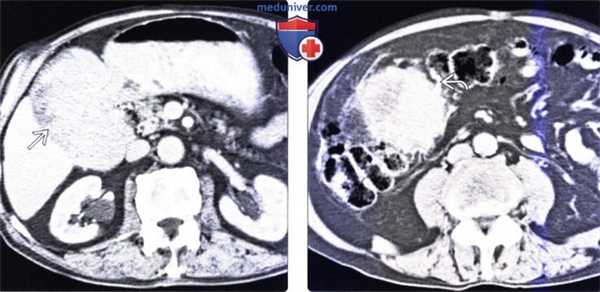

(Слева) На аксиальной КТ с контрастным усилением у мужчины 77 лет визуализируется боль -шое объемное образование, инфильтрующее и вызывающее утолщение в области малой кривизны от кардиального отдела до привратника. Определяются также метастазы в печени и надпочечнике, наряду с регионарной лимфаденопатией.

(Справа) На аксиальной КТ с контрастным усилением у этого же пациента определяется поражение селезеночной вены, приводящее к ее сужению и появлению околожелудочных коллатералей. Обратите также внимание на вторичное поражение чревных лимфатических узлов. (Слева) На аксиальной КТ с контрастным усилением у женщины 77 года с жалобами на раннее насыщение, отсутствие аппетита и потерю веса, визуализируется растянутый желудок, суженный в антральном отделе, где его стенка утолщена. Инфильтрация околожелудочного жира наряду с увеличением лимфатических узлов означает распространение опухоли за пределы желудка.